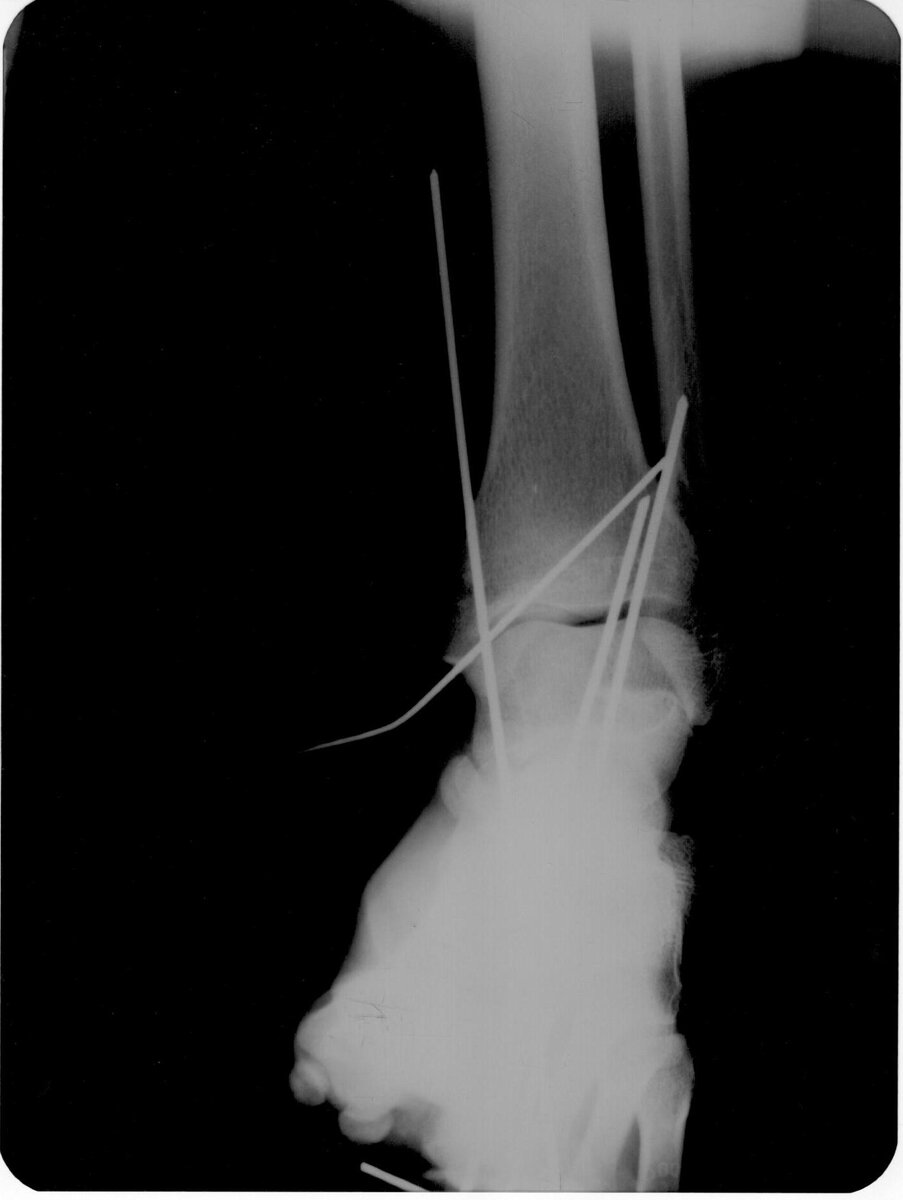

Благодарен хирургам, которым удалось без операции собрать мою ногу и зафиксировать её спицами. Причем один из них был интерном. Это было круто. Благодарю!